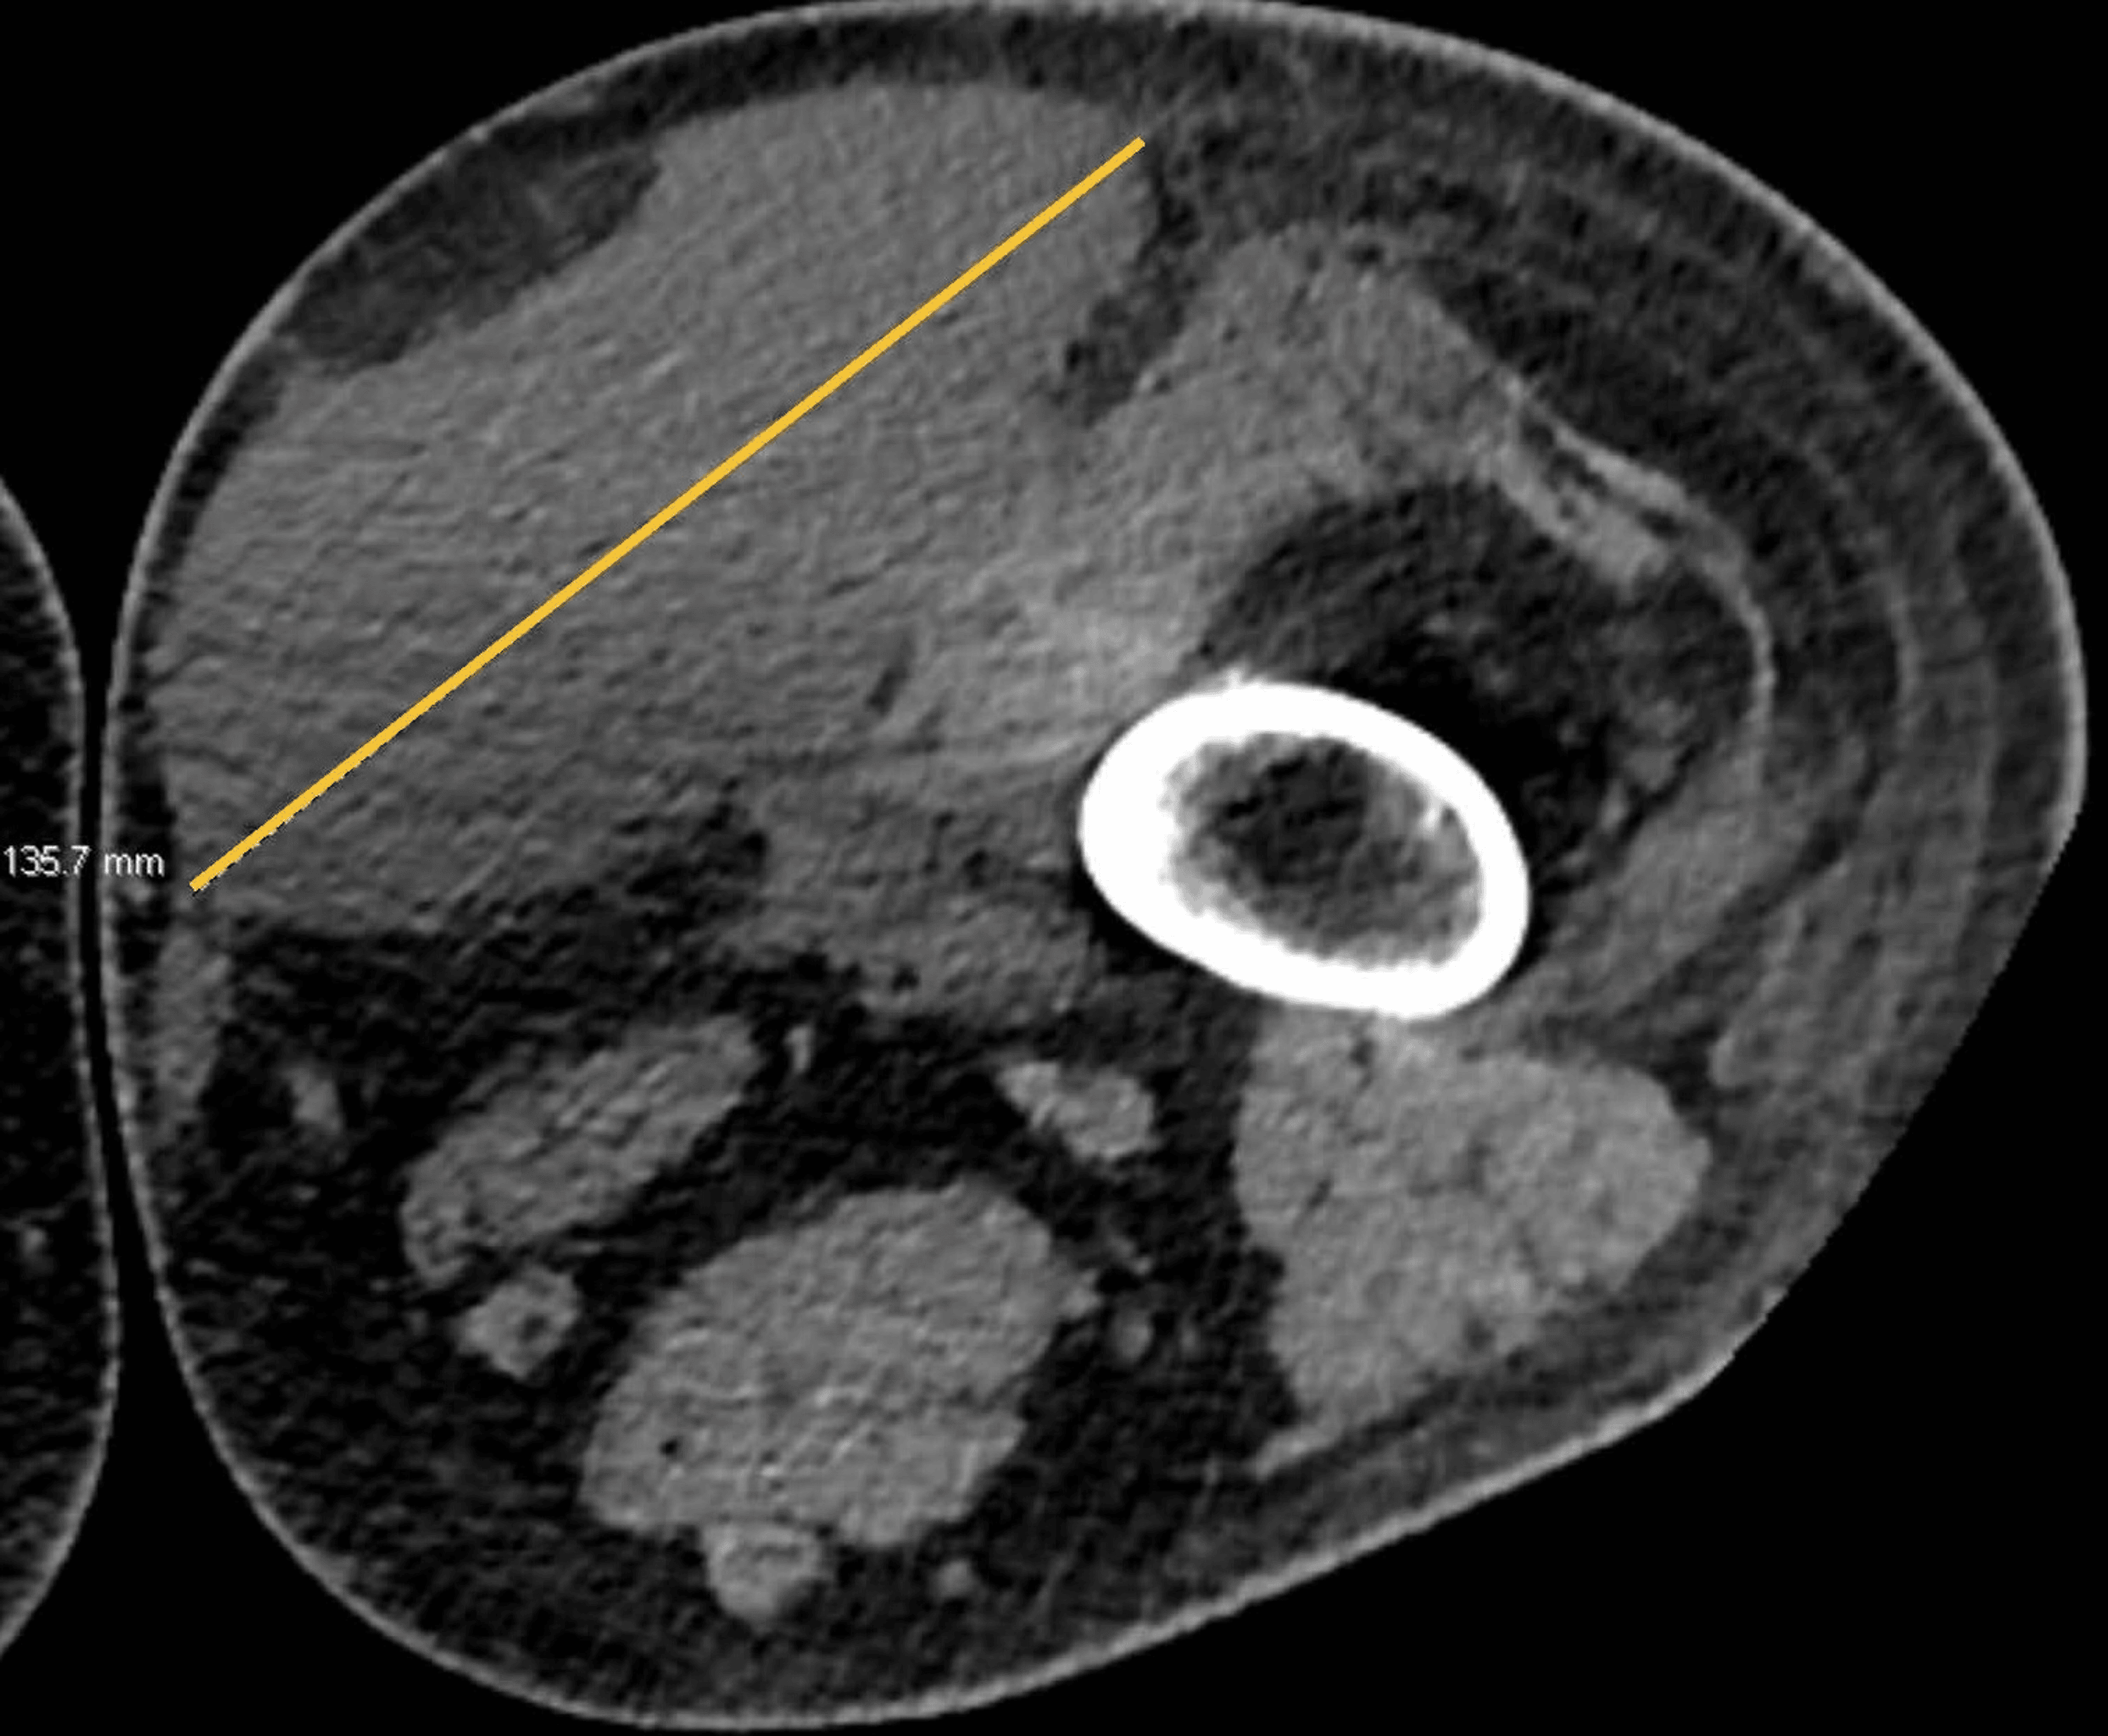

morel‐lavallée lesion is a closed soft tissue degloving injury caused by high‐energy violence, usually associated. surgical interventions such as open debridement, techniques to close dead space, negative pressure wound therapy,. The thigh, hip, and pelvic region are the most.

Presentation1, radiological imaging of morel lavallee lesion. Morel Level Lesion surgical interventions such as open debridement, techniques to close dead space, negative pressure wound therapy,. The thigh, hip, and pelvic region are the most. morel‐lavallée lesion is a closed soft tissue degloving injury caused by high‐energy violence, usually associated. Morel Level Lesion.

Presentation1, radiological imaging of morel lavallee lesion. Morel Level Lesion The thigh, hip, and pelvic region are the most. morel‐lavallée lesion is a closed soft tissue degloving injury caused by high‐energy violence, usually associated. surgical interventions such as open debridement, techniques to close dead space, negative pressure wound therapy,. Morel Level Lesion.